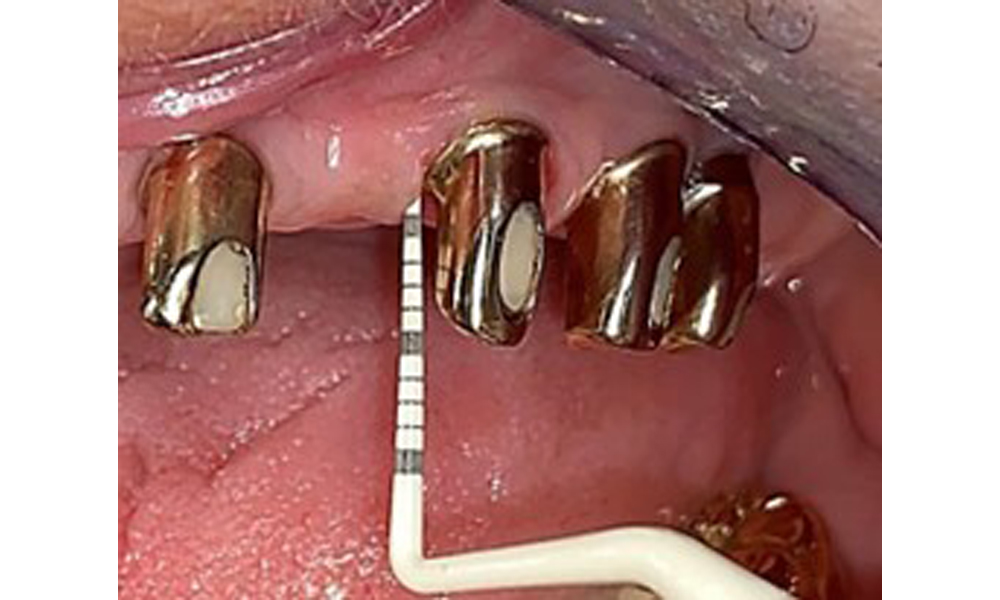

The dental findings are as follows: Combined removable implant and tooth-supported telescopic prostheses on implants 15, 13, 21, 23, 24, 25 and tooth 11 (Fig. 1, Fig. 2, Fig. 3). The patient was fitted with a fixed mandibular denture. Adequate bridges were present over 37 to 34 and 45 to 47 (Fig. 4), the crown margins were intact and there were no active caries. A composite filling with a marginal gap was present on tooth 43. There was mandibular gingival recession, exposing 1 to 3 mm of root surface. This also applies to 11.

Occlusal view: Maxilla with tooth and implant-supported telescopic prostheses.

Fig. 2: Occlusal view: Maxilla with tooth and implant-supported telescopic prostheses

The radiological findings show partially edentulous dentition with maxillary implants for teeth 15, 13, 21, 23, 24, 25 and a telescopic crown on tooth 11. Adequate mandibular bridges spanning 37 to 34 and 45 to 47 are present. 48 is impacted. There are suspected secondary caries distally on 43 and mesially on 44. 44 is restored with a non-radiopaque cavity lining. There is generalised horizontal bone loss of approx. 10% to 30% and localised vertical bone loss affecting teeth 22 and 42 (Fig. 5).

Panoramic X-ray image. The patient has a full set of adult teeth with generalised bone loss of between 10% and 30%. There is radiological suspicion of secondary caries on 44 and 43.

Fig. 5: Panoramic X-ray image. The patient has a full set of adult teeth with generalised bone loss of between 10% and 30%. There is radiological suspicion of secondary caries on 44 and 43.